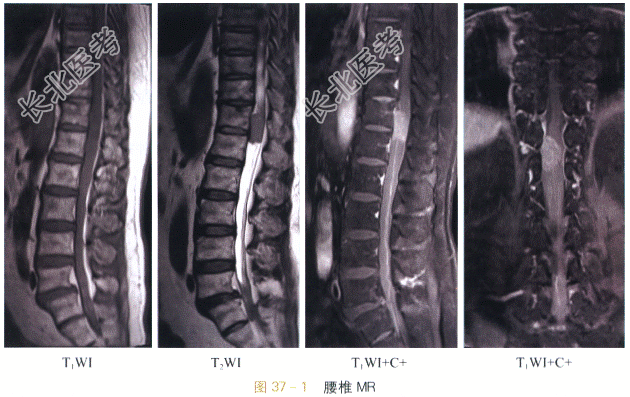

影像学资料如图37-1所示。

读片分析:腰椎矢状面、冠状面MR像示脊髓圆锥水平髓内病变:T₁加权像上等于脊髓信号,T₂加权像上,病变信号等于脊髓,信号均匀,肿瘤头端见大片状明显长T₂水肿信号,病变两侧蛛网膜下腔变窄。增强后MRI显示病变呈明显均匀强化,其边界显示清晰、锐利,水肿区无强化。